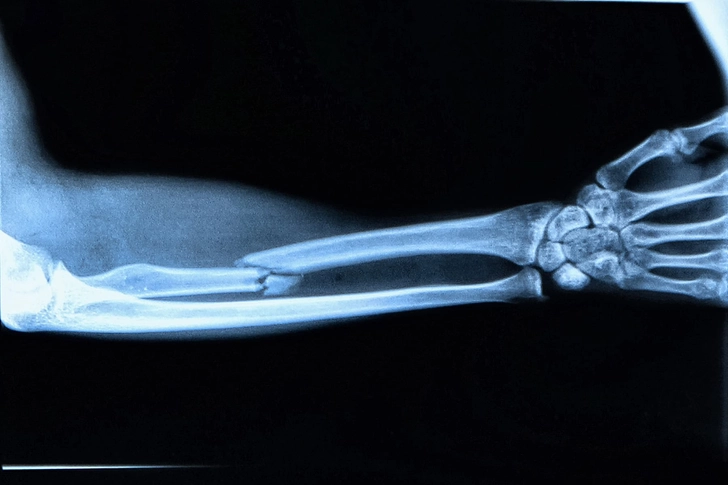

Broken Bone

When a bone cracks or breaks completely in two, you could have serious pain, swelling, and bruising. Older patients might fracture an arm falling from a standing height. Falls and collisions in sports and car accidents are more likely causes when you’re younger. Your doctor will try to get your bone straight again and then keep it still with a cast so it can heal. Some bad breaks may require surgery and screws or pins to set the bone.